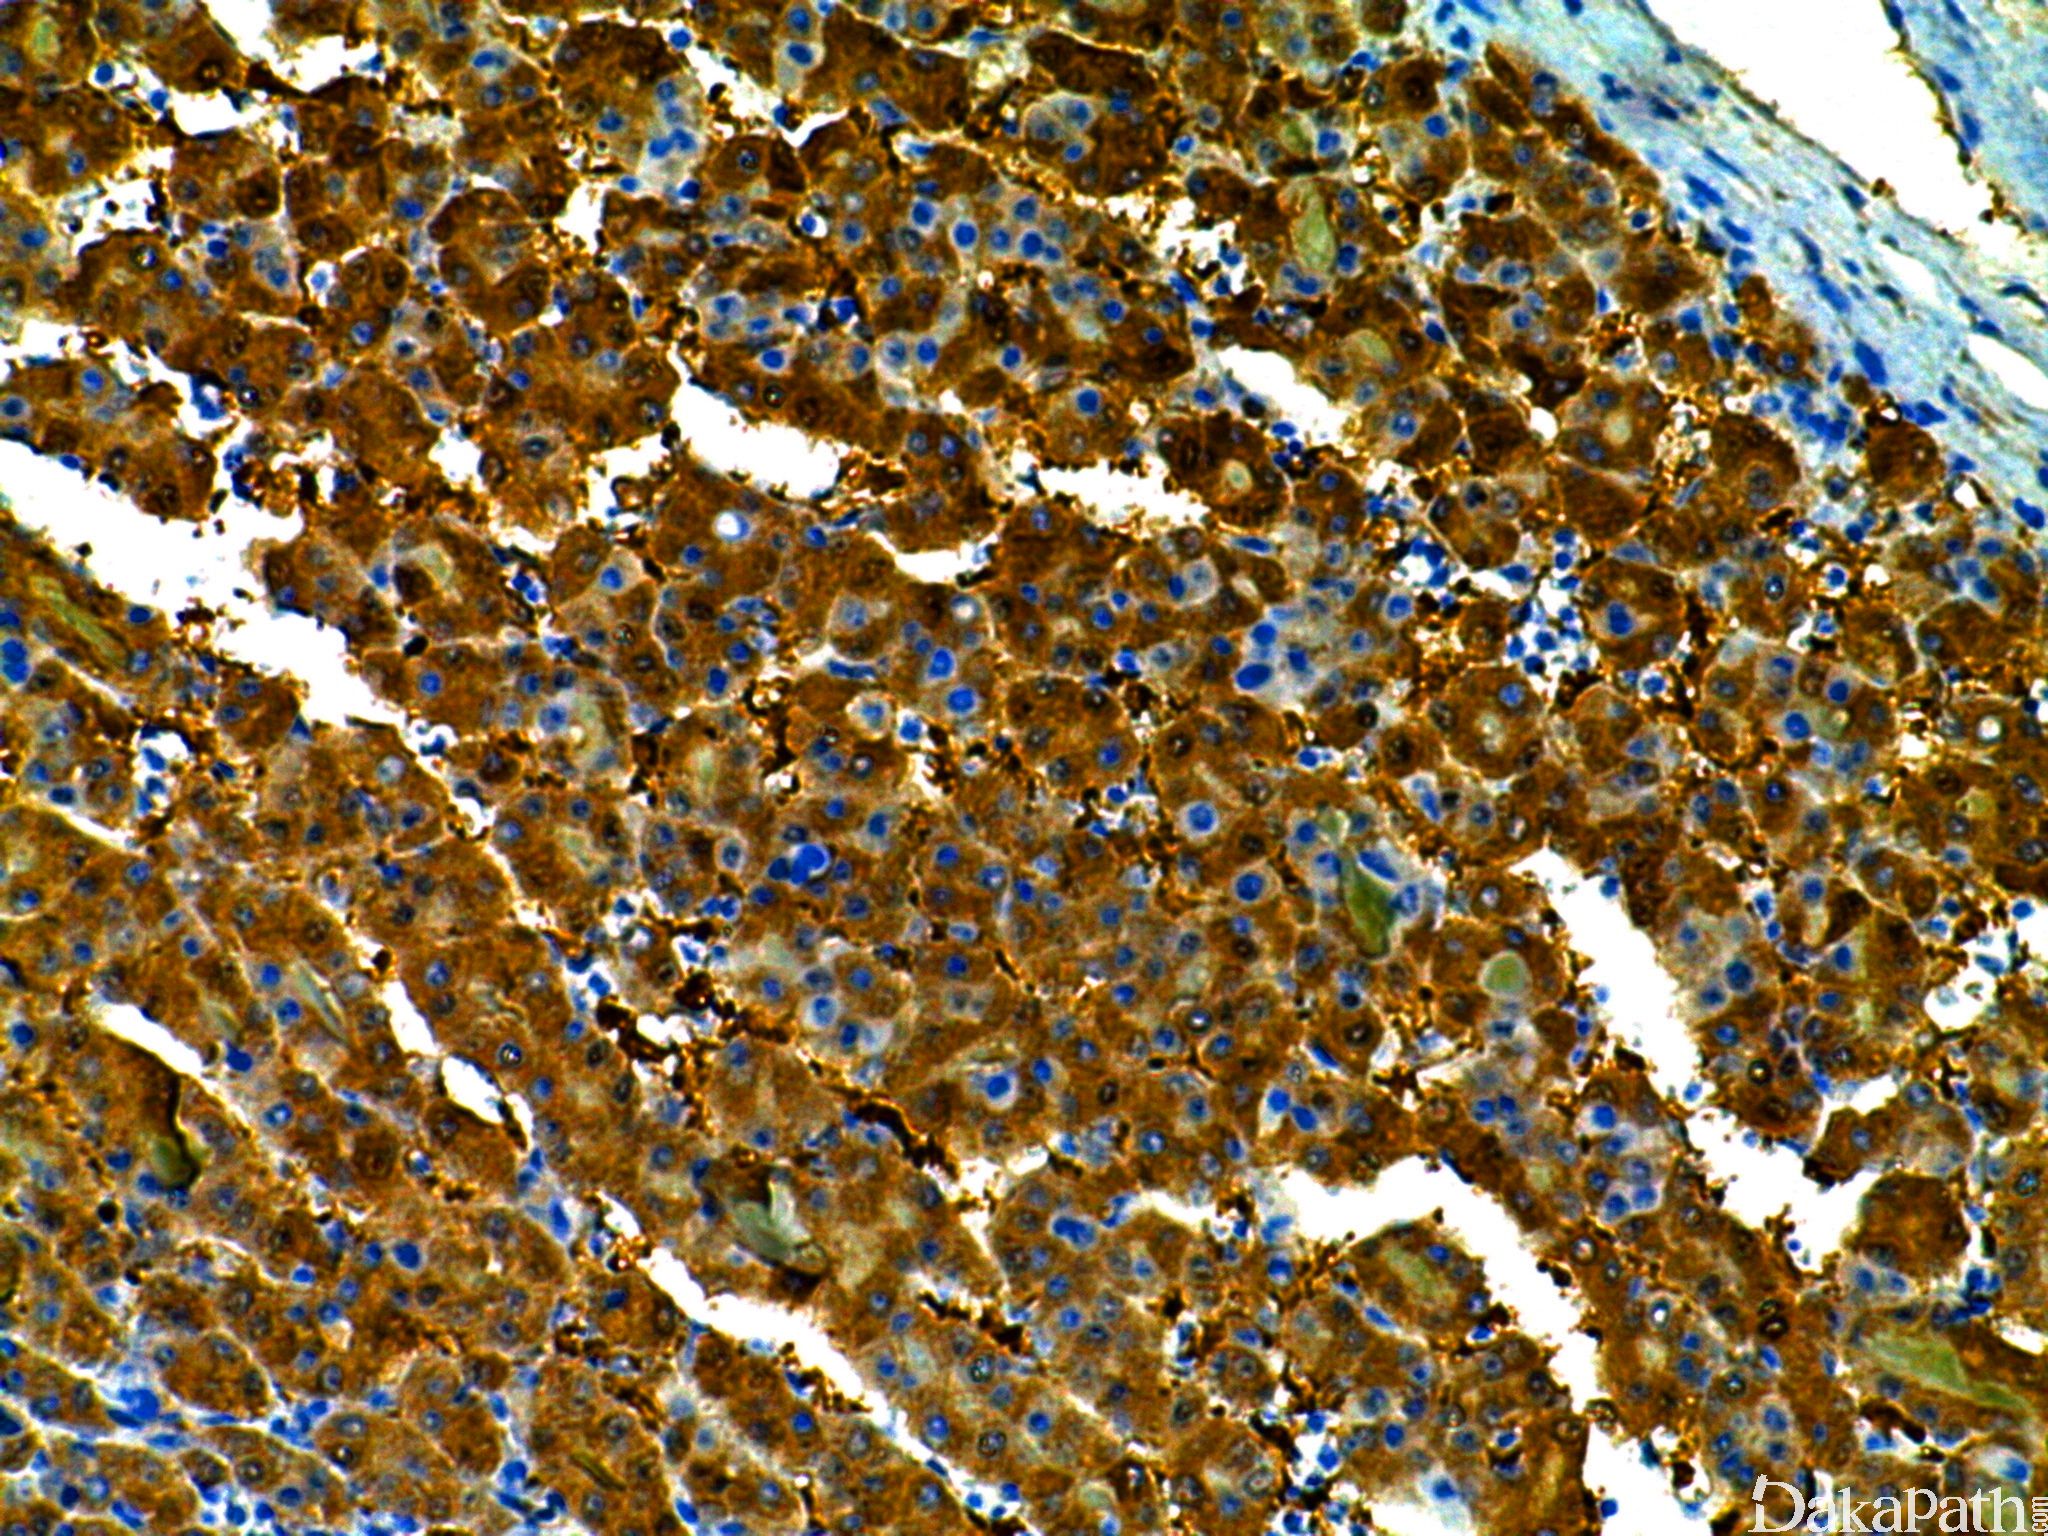

Arginase-1

尿素氮循环关键酶之一,在肝脏中发现,正常肝细胞中的表达具有很高的特异性,胆管上皮细胞、肝窦内皮细胞、血管内皮细胞及 Kupffr cell 不表达。是肝细胞腺瘤及肝细胞癌的特异性及敏感性指标(较 HepPar1 和 Glypican-3 更敏感和特异)。

信号定位: 胞浆、胞核

肝细胞癌的敏感性标记,用于原发性肝细胞癌与转移性癌及胆管癌的鉴别诊断。